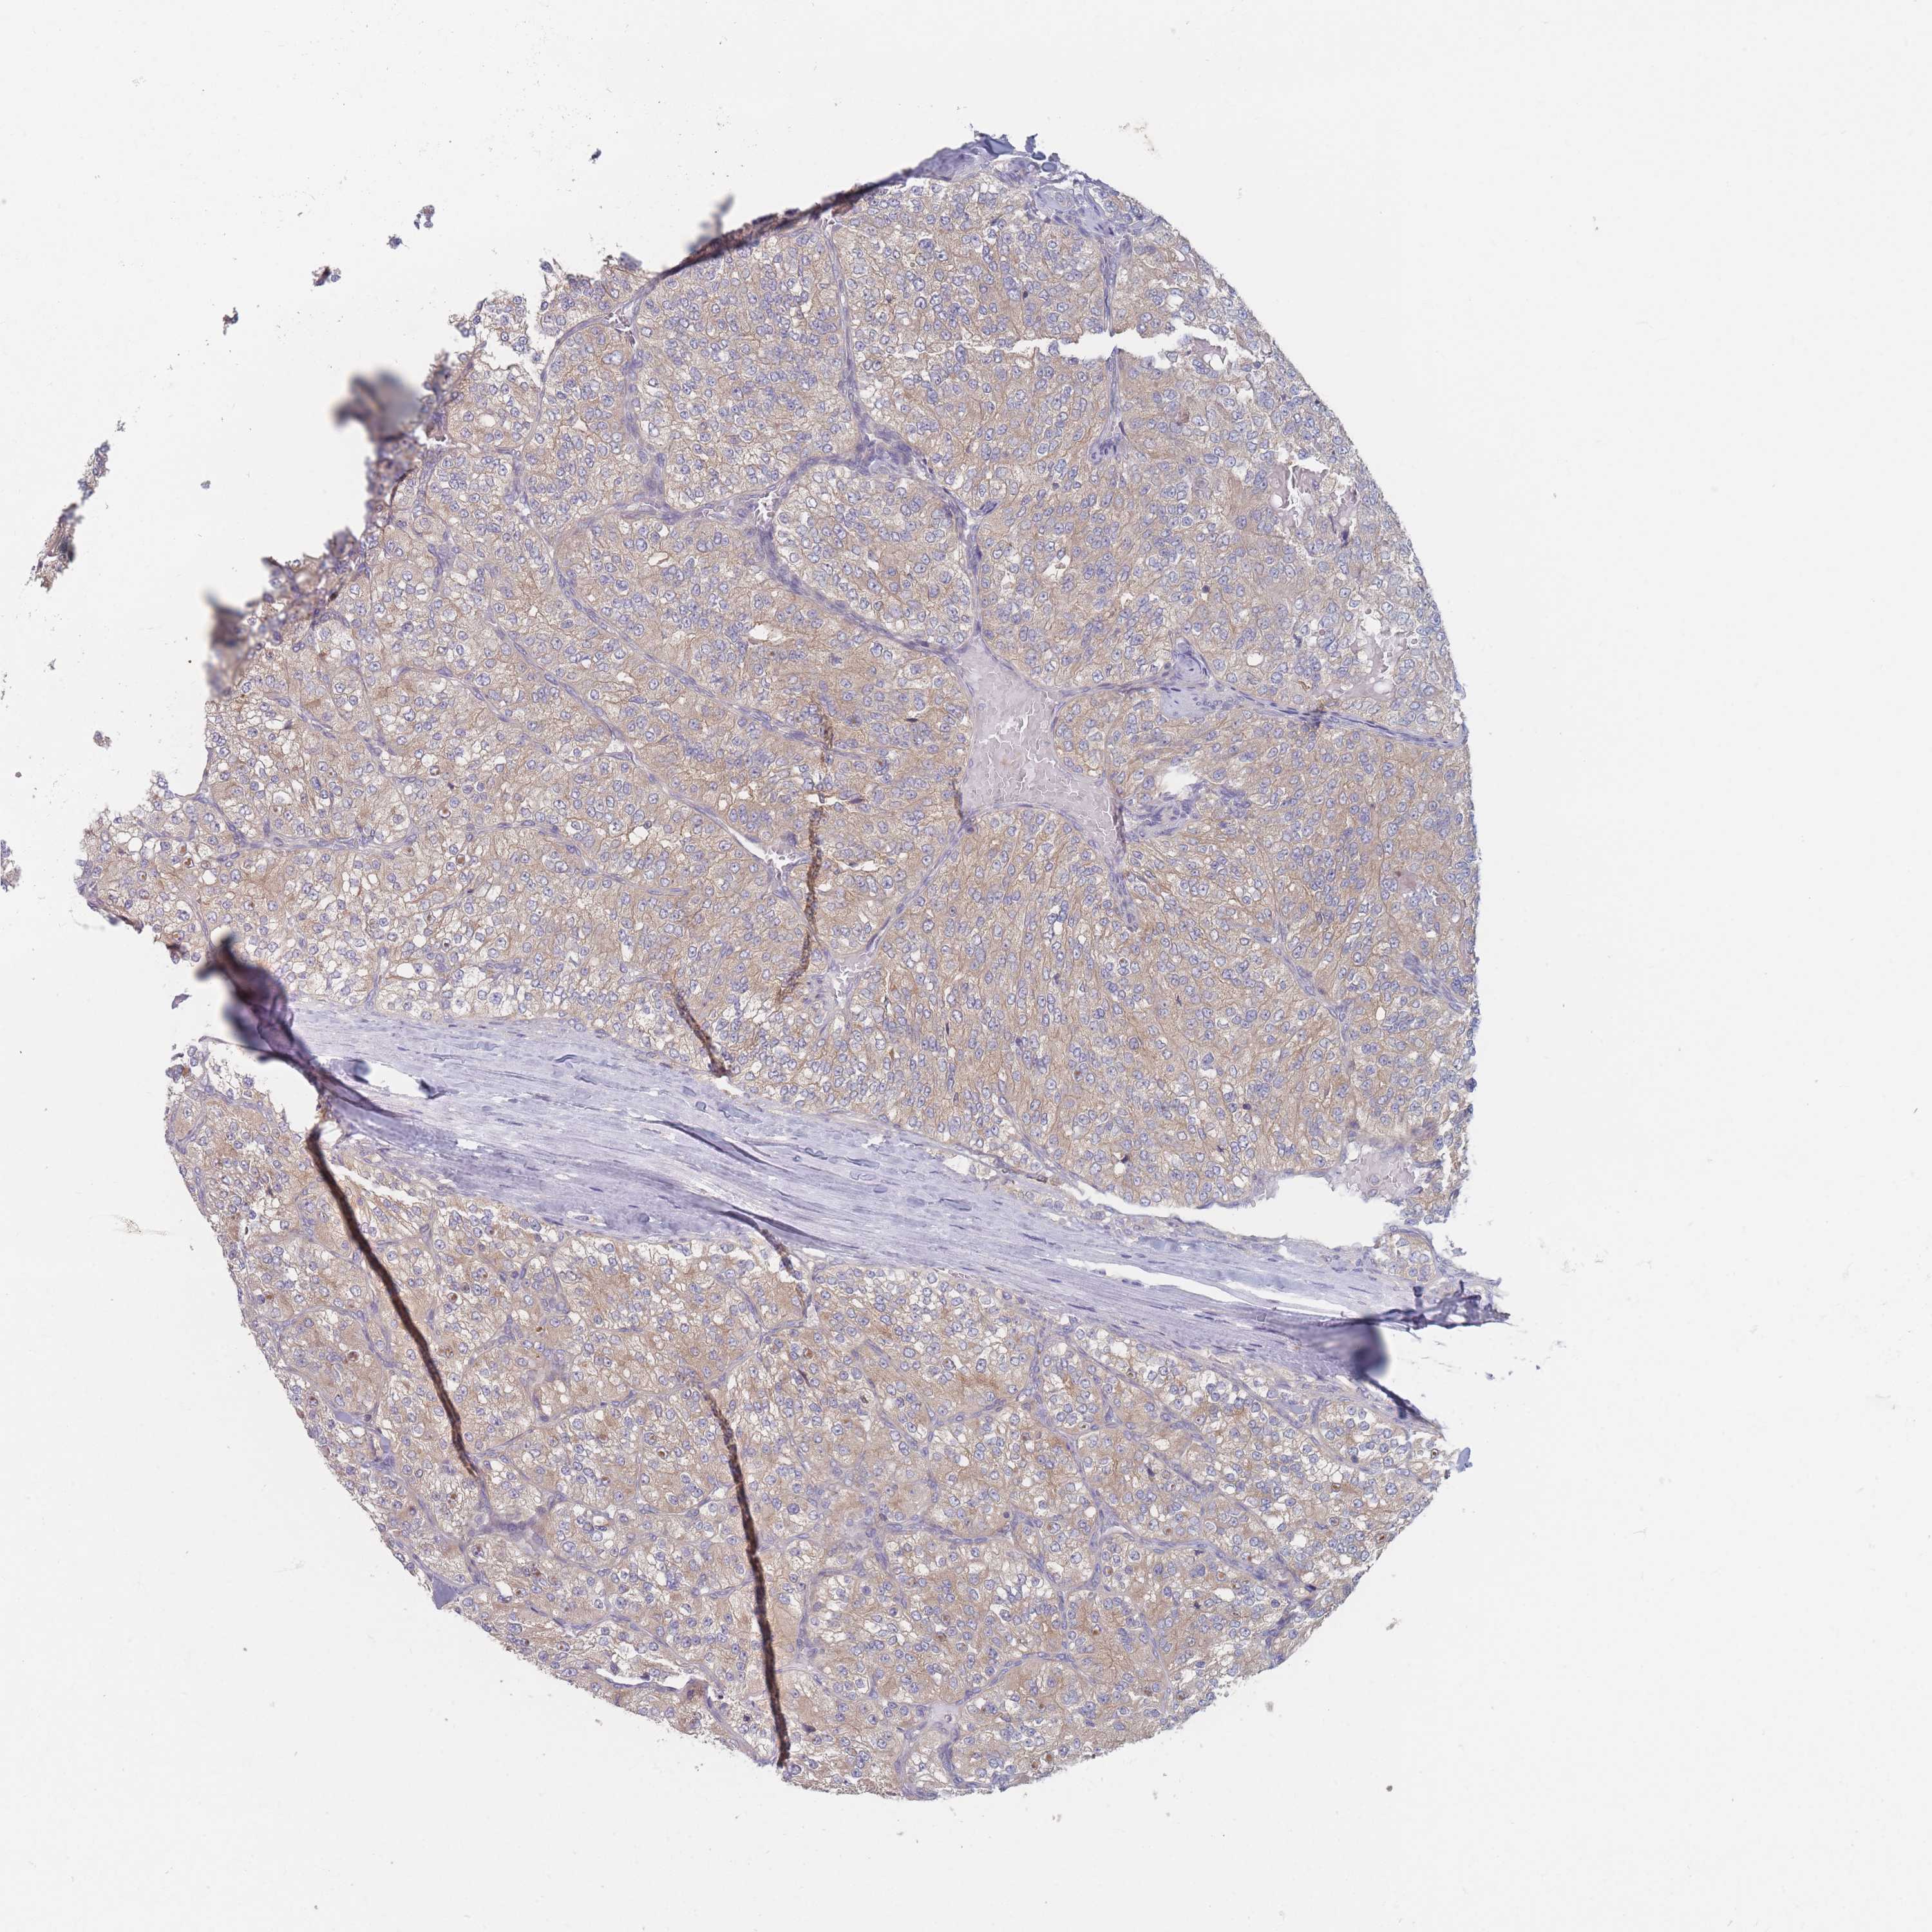

CANCER RENAL CANCER Show tissue menu

KICH TCGA KIRC TCGA KIRC VALIDATION KIRP TCGA PROTEIN RCC CPTAC PROTEIN EXPRESSION